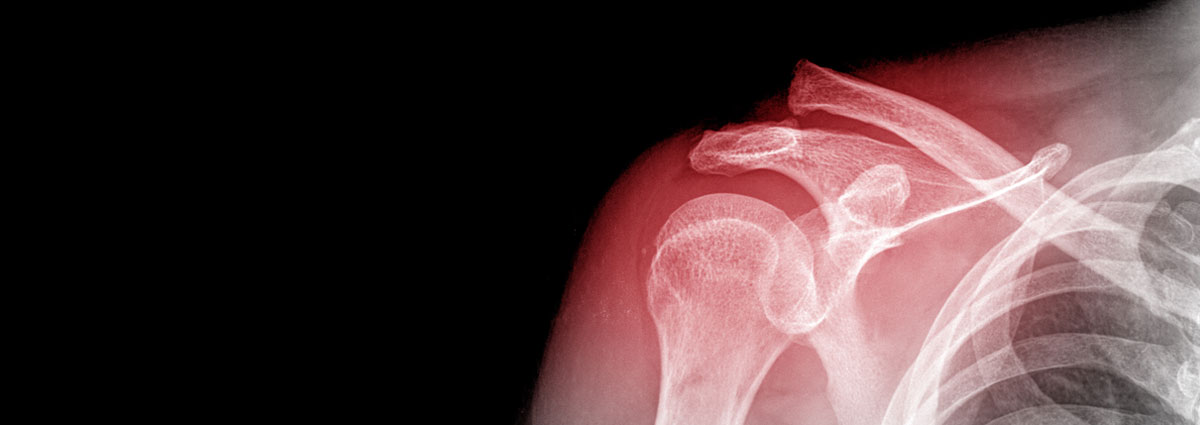

El hombro es la articulación que conecta el tronco con el brazo y está formado por tres huesos: escápula u omóplato, clavícula y húmero. Envuelto por cartílago que permite un movimiento suave e indoloro, el hombro se divide en dos cavidades articulares, el espacio subacromial (dónde se encuentran los tendones del manguito rotador, y cuya función es estabilizar la articulación del hombro al elevar el brazo y realizar la flexión y rotación externa del brazo) y la articulación gleno-humeral (donde se encuentran los ligamentos que actúan a modo de refuerzo y que dan estabilidad al hombro evitando la luxación articular).

- Fracturas

Las fracturas son lesiones producidas por un traumatismo de mayor intensidad que origina una rotura del hueso. Las fracturas en la articulación del hombro se pueden producir en cualquiera de los 3 huesos que lo forman:

- Fractura de la clavícula: suelen producirse por una caída sobre el hombro, el cual transmite la fuerza deformante hacia la clavícula produciendo su fractura.

- Fractura de la escápula u omóplato: son poco frecuentes y se suelen producir en traumatismos de gran energía en los que se ven afectados hombros, tórax y columna.

- Fractura de la cabeza humeral: también implican un traumatismo de gran energía. Esta lesión se da con más frecuencia en gente de edad avanzada debido a la disminución en la densidad ósea.

El daño y el tipo de fractura marcarán el tratamiento a seguir (reposo, medicación, etc). Si la fractura es grave, será necesaria una intervención quirúrgica para colocar de nuevo los huesos en su posición normal.